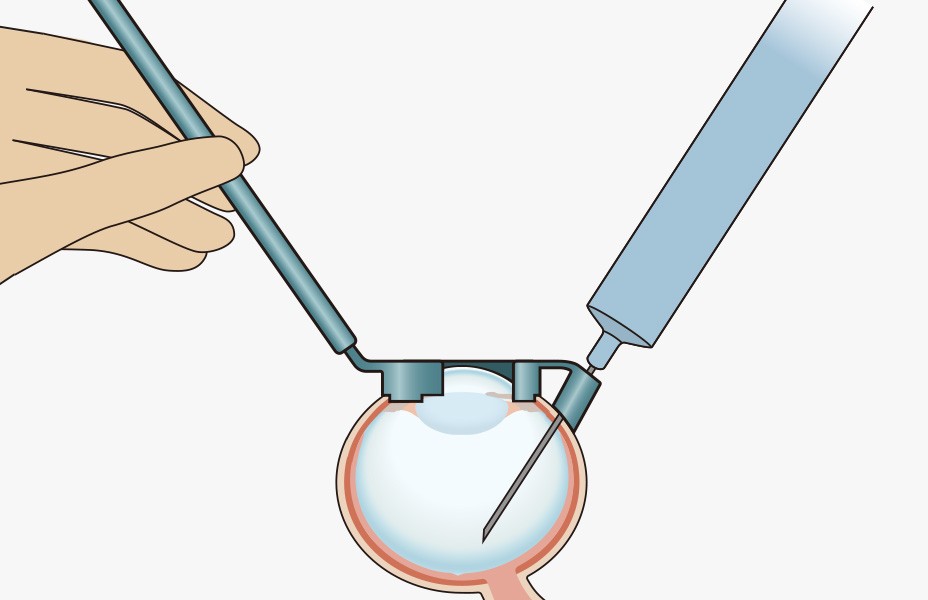

手順1:眼球の固定

■十分に開瞼します。

■角膜を中心に輪部全周にしっかりと押し当て注射ガイドを固定します。

手順2:注射針の刺入

■26G〜30G×3/4インチの鋭針をガイド孔に沿って刺入します。

■刺入部は輪部から3.5〜4.0mmになります。